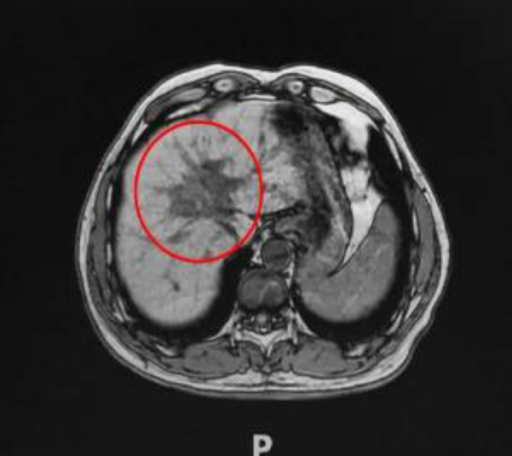

Ablation site with clear visible boundary on imaging